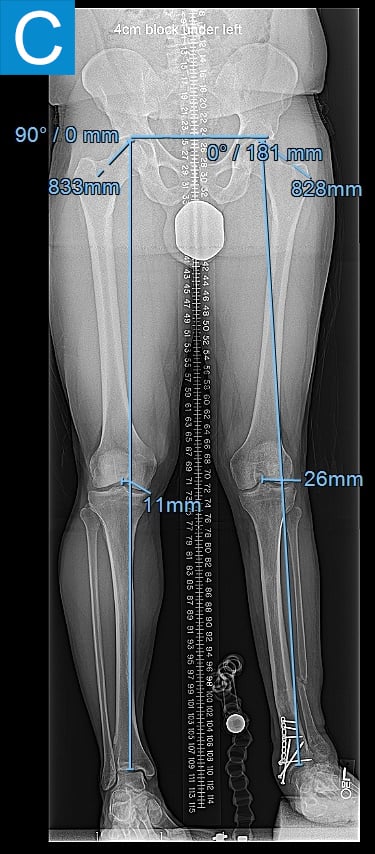

Examination (Figure 1) was notable for a valgus left foot and ankle, with reduced muscle bulk versus the right. His gait was antalgic on the left with minimal knee flexion throughout and no ankle push off (Video 1). Radiographs showed the left leg to be 4 cm shorter than right, with genu valgum, malunion of the lengthened tibia, the recently placed distal tibia fixation, and a ball and socket ankle with short fibula featuring nonunion and malunion at different locations, characteristic of fibular deficiency. He was counseled that a pain-free limb could be provided via reconstructions including hardware removal, distal tibia osteotomy, hindfoot fusion, distal femur osteotomy, and lengthening. He wanted a faster option for painless, high-demand function and asked if he could have tibial osseointegration instead. This was indeed a reasonable option for him. He elected to defer distal femur osteotomy unless the knee remained symptomatic.

Figure 1. Preoperative clinical photos and radiographs. (A) Front and (B) rear views of the patient show a short left leg with foot and ankle valgus and genu valgum and a left calf with reduced musculature. (C) Standing coronal and (D) lateral tibia radiographs depict the prior distal tibia lengthening with fibula nonunion, ankle fracture with fixation, ball and socket ankle, and short fibula. Also note the genu valgum.